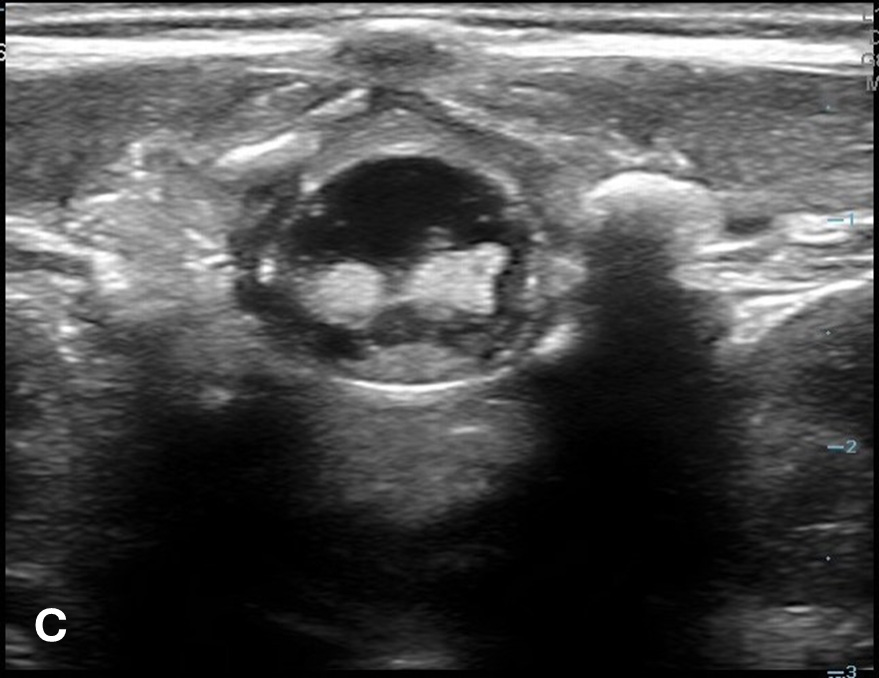

The transverse view should also be obtained to verify landmarks and identify any overlying vessels or hematomas (from prior attempts) to avoid. The transducer is rotated to the transverse position on the lower back and moved caudally over the spinous processes to locate the CM, which is a hypoechoic structure positioned in the center of the spinal canal. At higher levels of the CM, the ventral roots and dorsal roots can be identified, which are surrounded by the anechoic CSF. Next, gradually move the transducer caudally and observe the CM decreasing in size while being encircled by the hyperechoic fibers of the CE. (Figure 2) Once this sonographic landmark is identified, locate the center of the transducer and mark the corresponding area on the skin, aligning it with the center of the spinal cord. Subsequently, draw lines from both markers in both planes and utilize the point of intersection as a guide for inserting the LP needle. To enhance visualization of the spinal cord’s vascular supply, and avoid a space with any overlying vessels that may cause a traumatic tap, it is advisable to apply color Doppler in both the sagittal/longitudinal and transverse views.9 (Figure 3)

Figure 2 - Corresponding US image showing spinal canal structures in transverse view:

Figure 2 - Corresponding US image showing spinal canal structures in transverse view. 2A-B: The caudal portion of the transverse view shows DR (dorsal roots), VR (ventral roots), CSF (cerebrospinal fluid), and CM (conus medullaris). 2C-D: The probe is moved caudally demonstrating the tapered CM (orange dotted circle), CE (cauda equina, hyperechoic structure surrounding the CM) and a pocket of CSF. 2E-F: Demonstrate the disappearance of the CM, and the pocket of CSF becoming larger as the probe was moved caudally. The blue circle is the entire dural sac encircling the spinal canal.